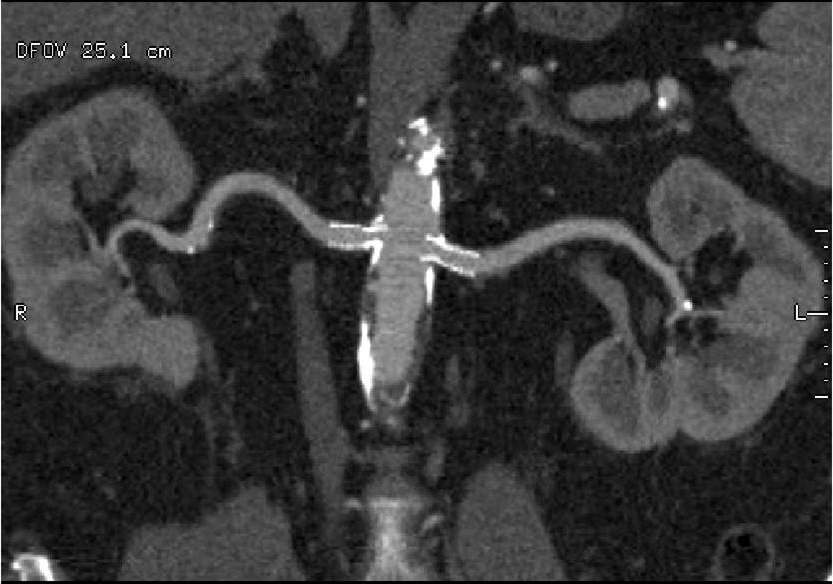

CTA and MRA are both capable of diagnosing renal artery stenosis. Both methods can identify anatomic variations, atherosclerotic lesions at the origin of the vessels or at distal segments on the artery. These techniques not only show the contour irregularities and the narrowed lumen, but they are also able to reveal the secondary parenchymal lesion of the kidney. However, in patients with decreased renal function, both types of contrast materials should be avoided or applied only with care.

Image

Contrast enhanced MR angiography

Control CT angiography after stent implantation to correct a bilateral arterial stenosis

Fig. 18., 19.: Renal artery stenosis